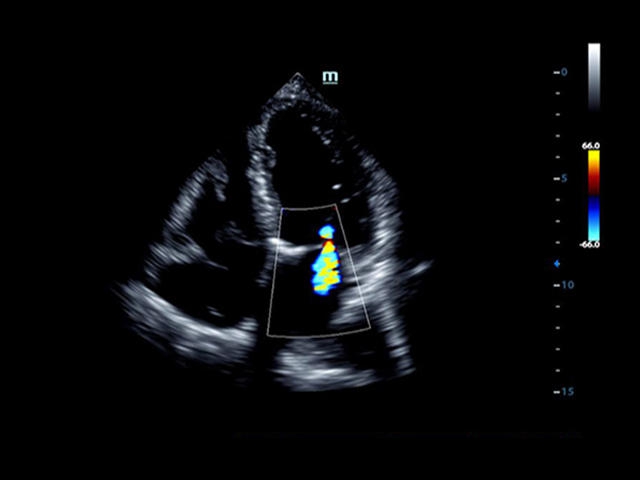

Mindray DC-8 Exp – это ультразвуковой аппарат с архитектурой mQuadro и функцией эластографии Natural Touch. Он оснащен высококлассным 21-дюймовым TFT-монитором с разрешением Full HD. Данный аппарат представляет интерес для специалистов, занимающихся обследованием мягких тканей с использованием эластографии. Режим объемного 4D-сканирования позволяет получать максимально точные диагнозы, сокращая количество неэффективных процедур.

Mindray DC-8 Exp оснащен новым поколением датчиков с увеличенным количеством элементов и инновационной технологией "3T". Это позволяет достичь высокой детализации и качества изображения. Благодаря новейшей технологии iFlow, можно визуализировать даже самые мелкие сосуды и кровеносные пути.

Сверхширокополосная нелинейная обработка изображений снижает визуальные шумы на 30% по сравнению с другими системами. Технология iClear позволяет устранить зернистость изображения, а iBeam (технология пространственного компаундинга) обеспечивает высокое качество сканирования органов и тканей под различными углами.